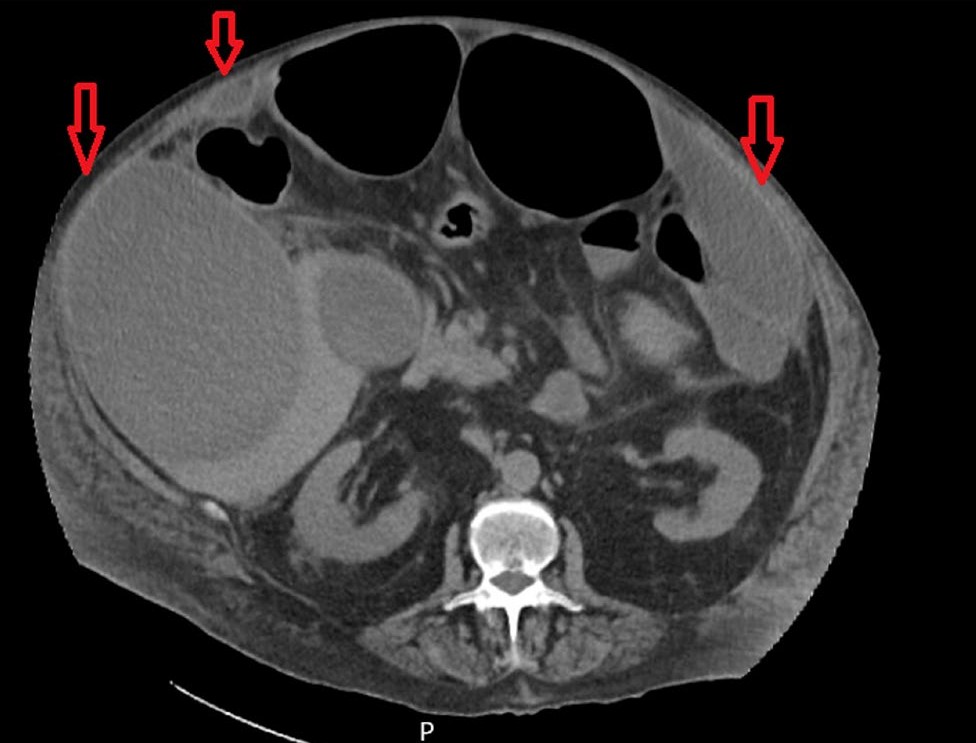

• Exuberant Intra-Abdominal Abscesses Secondary to Streptococcus Anginosus: A Diagnostic and Therapeutic Challenge

José Santos, Jorge Leitão, Arsénio Santos, Lèlita Santos

95-100

DOI: https://doi.org/10.60591/crspmi.390